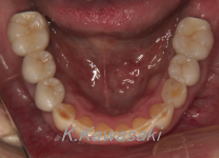

「入れ歯が痛くてかめない」と来院されました。

まだ若いためしっかりとインプラントで噛みあわせの回復をする事にしました。 |

| 上あごに4本、下あごに5本のインプラントを植立しました。 |

上あご→磁石を使い落ちない入れ歯を作りました。 |

上あごの総義歯には触感の良い薄い金属を使いました。 |

下あご→歯のない場所にインプラントを植立しました。 |